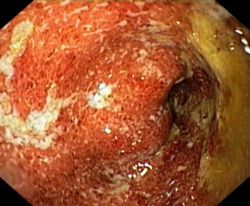

Неспецифический язвенный колит: симптомы, диагностика, диета

Неспецифический язвенный колит – это хроническое небактериальное воспалительное заболевание толстого кишечника с образованием в нем язв. В детском возрасте оно наблюдается относительно редко и протекает крайне тяжело, волнообразно. Мужчины болеют им реже, чем женщины.